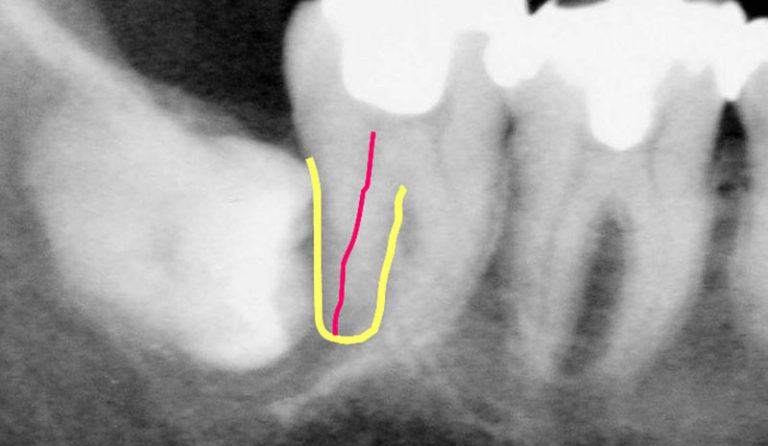

さあ、次のレントゲン写真を見てみましょう。

赤い線を引いているのは歯の神経です。

わかりやすく手前の7番目の歯の後ろ側の根と神経血管部分にラインを引いています(本来は右の歯のように神経血管が通っているトンネルの状態ですので、黒い線となって写ります)。

「親知らず」8がお隣の7番目の歯、6番目の歯に対して横にむいてきてるわけですね。

さあ、この親知らず放置しておくとどうなると思いますか?

歯の神経が圧迫されて痛くなっていくのです。手前の歯に穴をあけていくのです。

この親知らずは横に倒れていますから、自然に何十年待っていても口の中から見える部分まで絶対に生えてきません。

ほうっておいても上向きに出てこないのです。